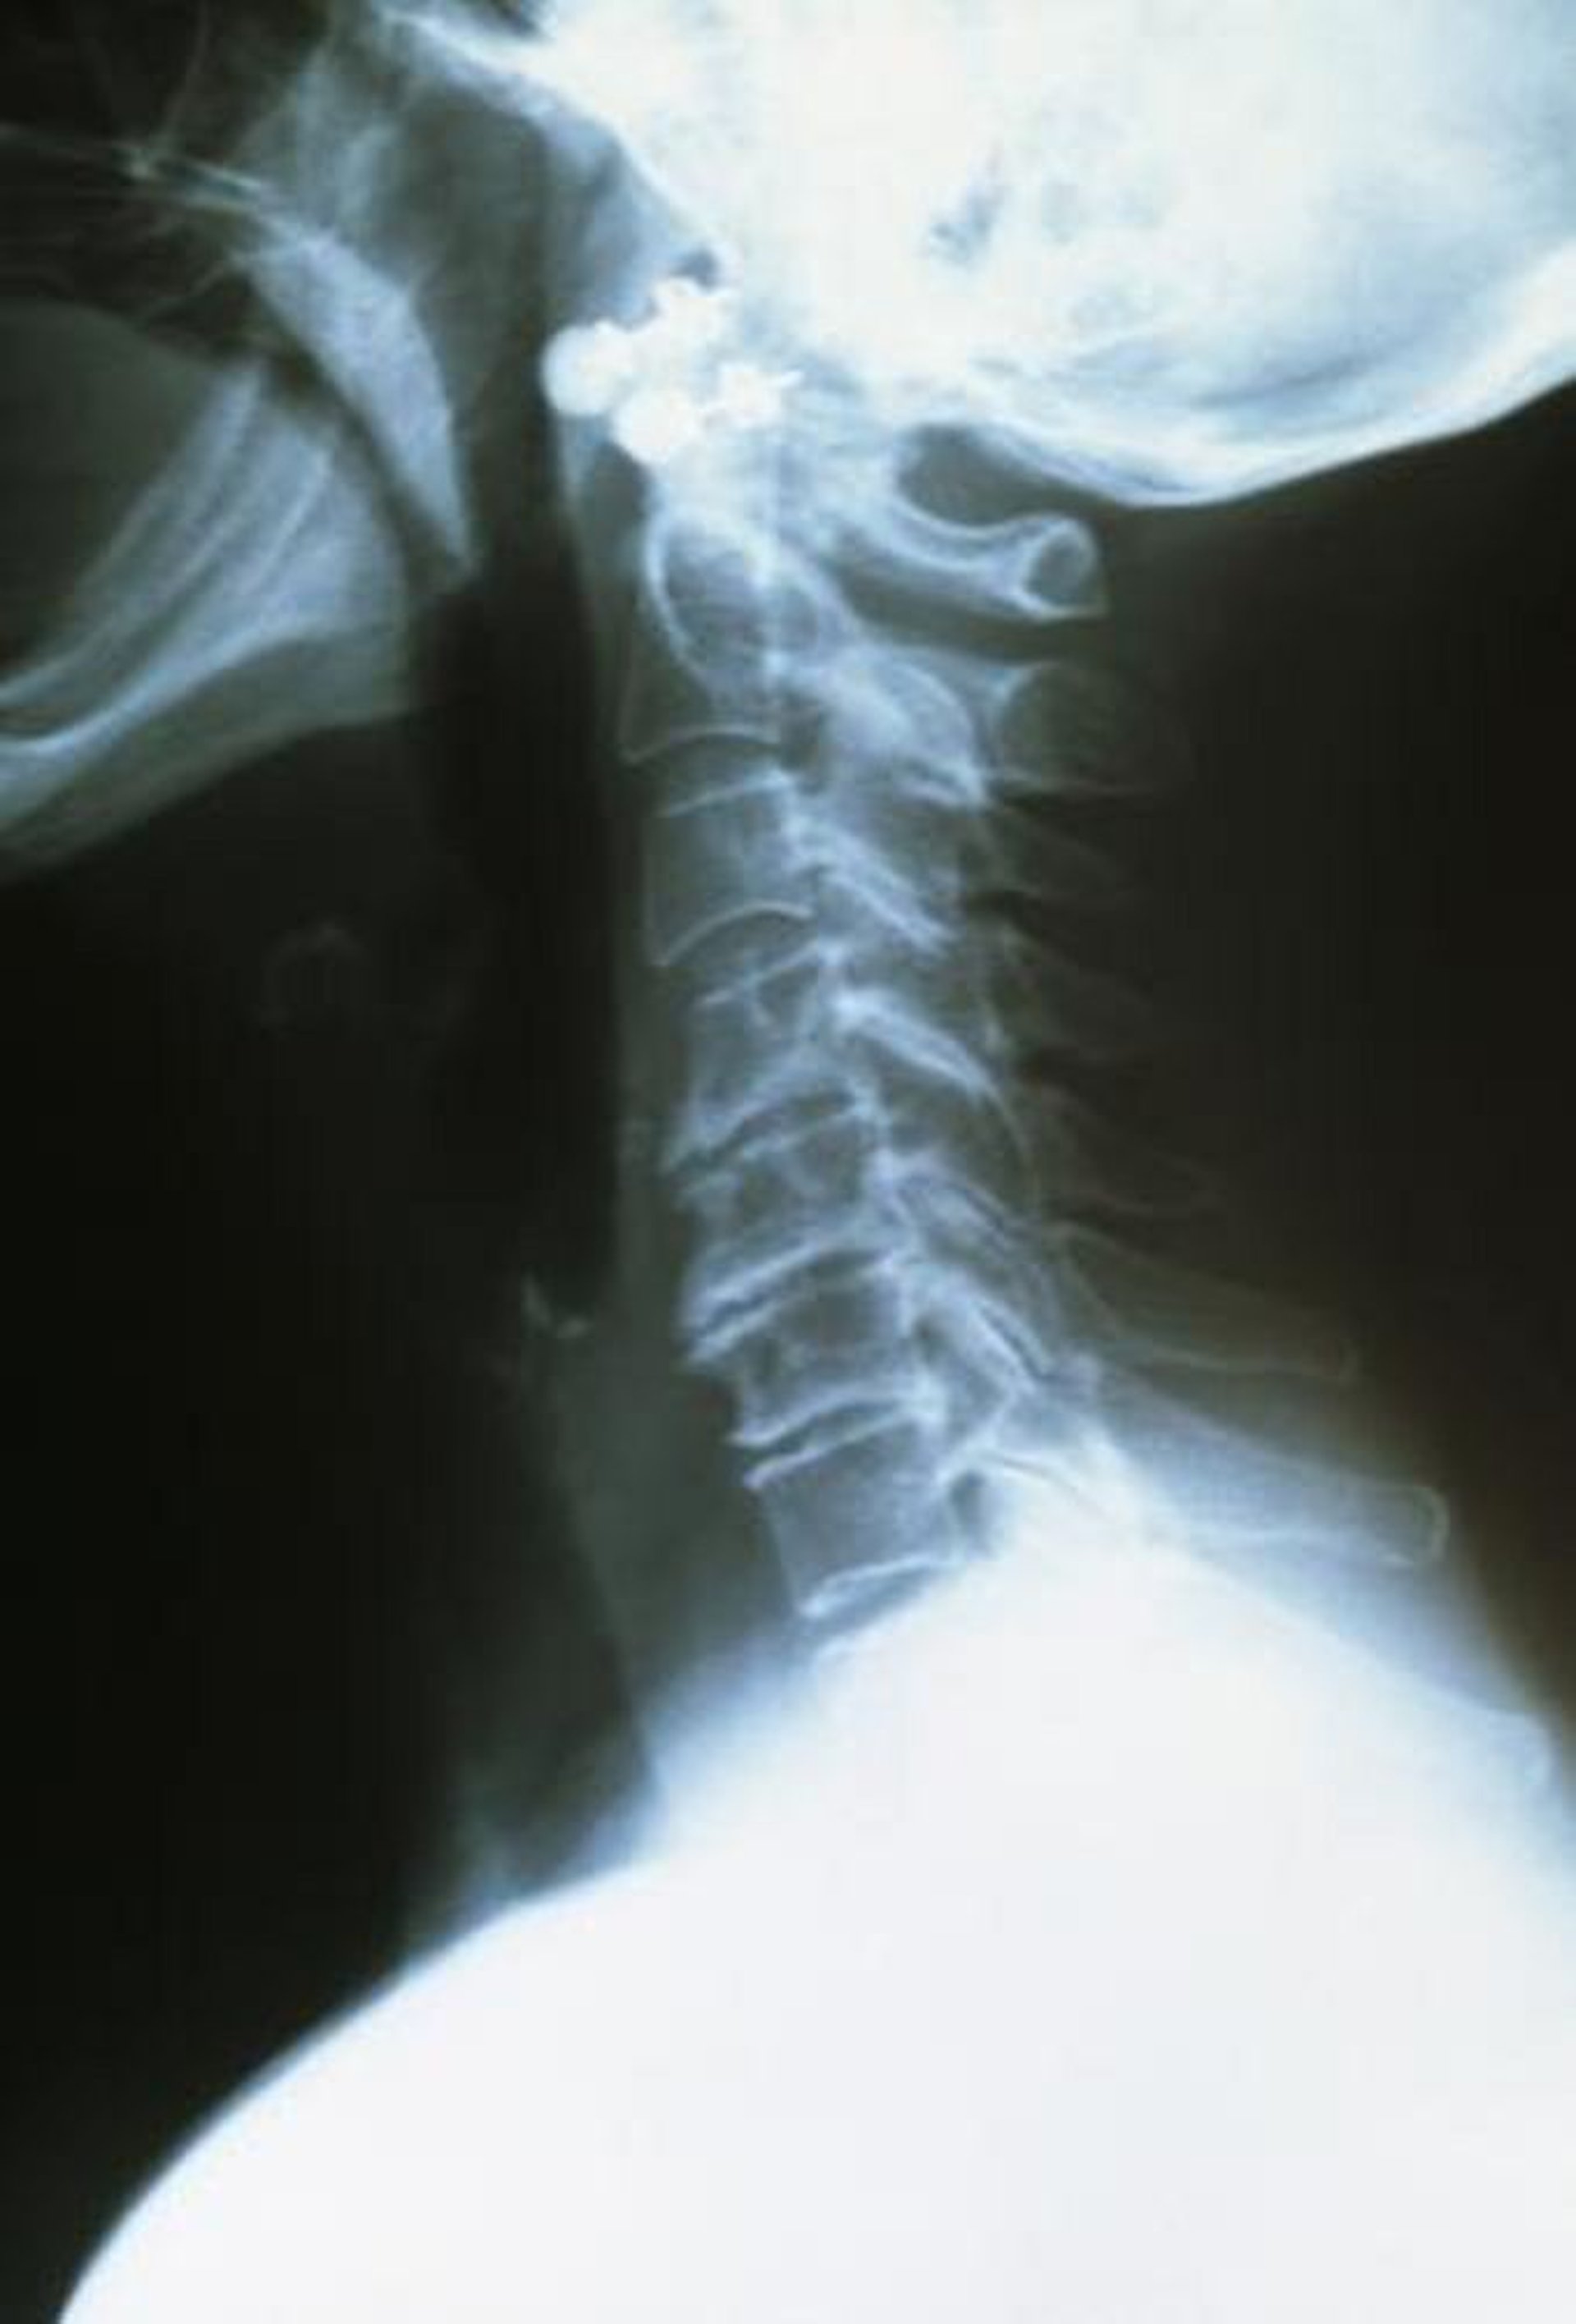

The upper cervical vertebrae are healthy, well spaced, and smooth edged. The arthritic lower vertebrae are closer together and have rough and ragged edges.

DR P. MARAZZI/SCIENCE PHOTO LIBRARY